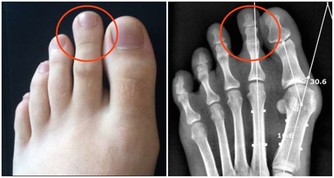

3、保護手足,自秋而始

秋季氣候乾燥,人的皮膚容易因缺水而皸裂。

糖尿病病人可選擇適合自己皮膚的潤膚霜,不宜使用含甘油的護膚品,因為甘油會使皮膚脫水。

每天洗足後,應塗抹含維生素E的保護膏,並按摩足部15~20分鐘。